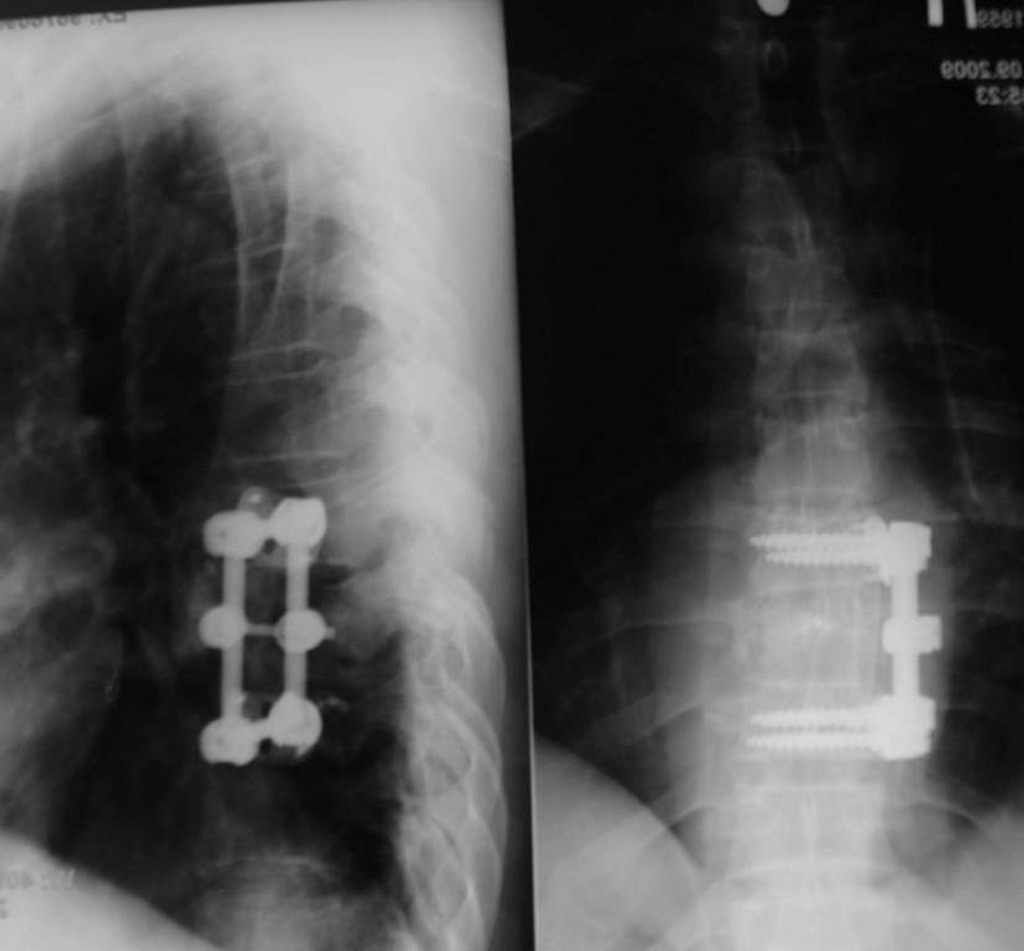

Компьютерная томография перелома позвонка.

В арсенале хирургов-вертебрологов в настоящее время есть все необходимое для решения этих задач: костный цемент и различные биоматериалы для вертебропластики, транспедикулярные и крючковые системы для задней фиксации, передние пластины, протезы тел позвонков, межпозвонковые импланты. Это дает возможность выполнить весь спектр операций при травмах позвоночника.

Операция по восстановлению передней опорной колонны поврежденного позвонка, передняя винтовая фиксация.